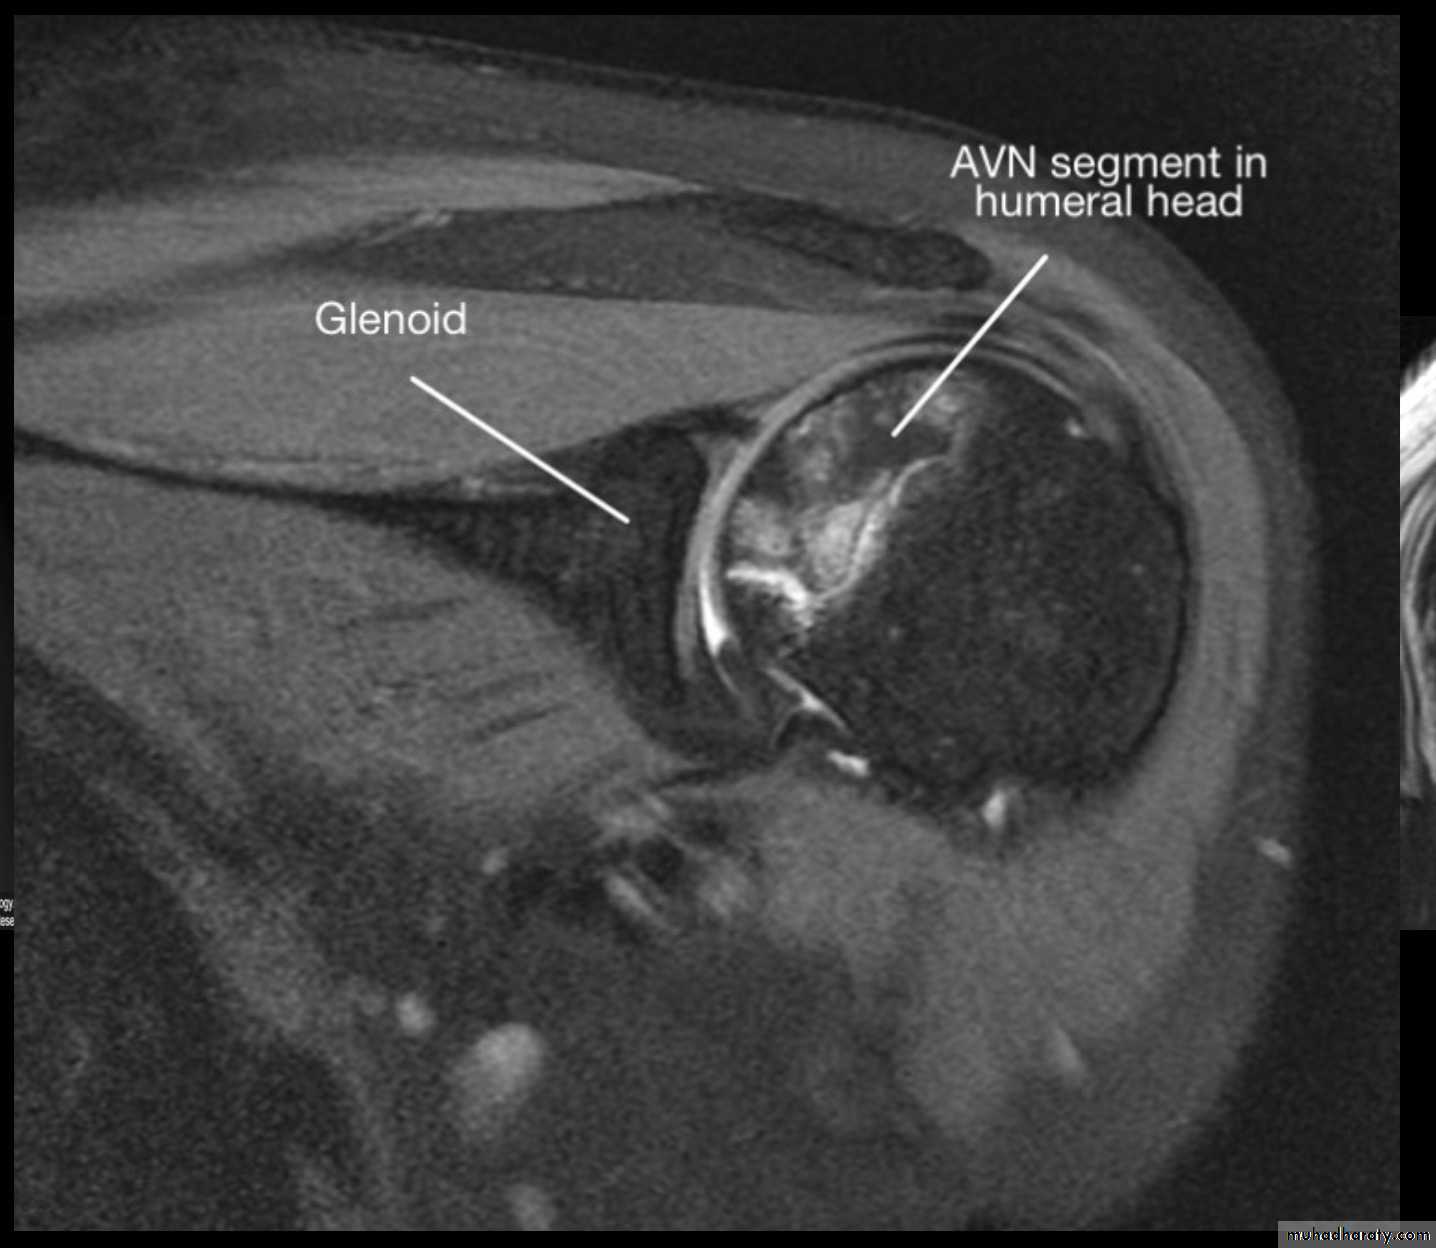

4_AVASCULAR NECROSIS

43

44